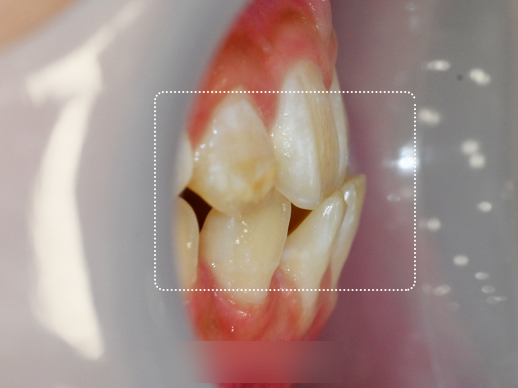

위턱보다 앞으로 돌출되어 나와있던

아래턱이 점점 후방으로 견인하여

올바른 교합 관계로 변하고 있음을 볼 수 있는데요.

또한 앞니 사이에 비어 보였던 공간들을

이동 과정을 통해 앞으로 잘 모아줍니다.

그러면서 맞지 않던 가운데 정중선 라인을

점점 잡혀져 가고 있음을 확인 가능합니다.